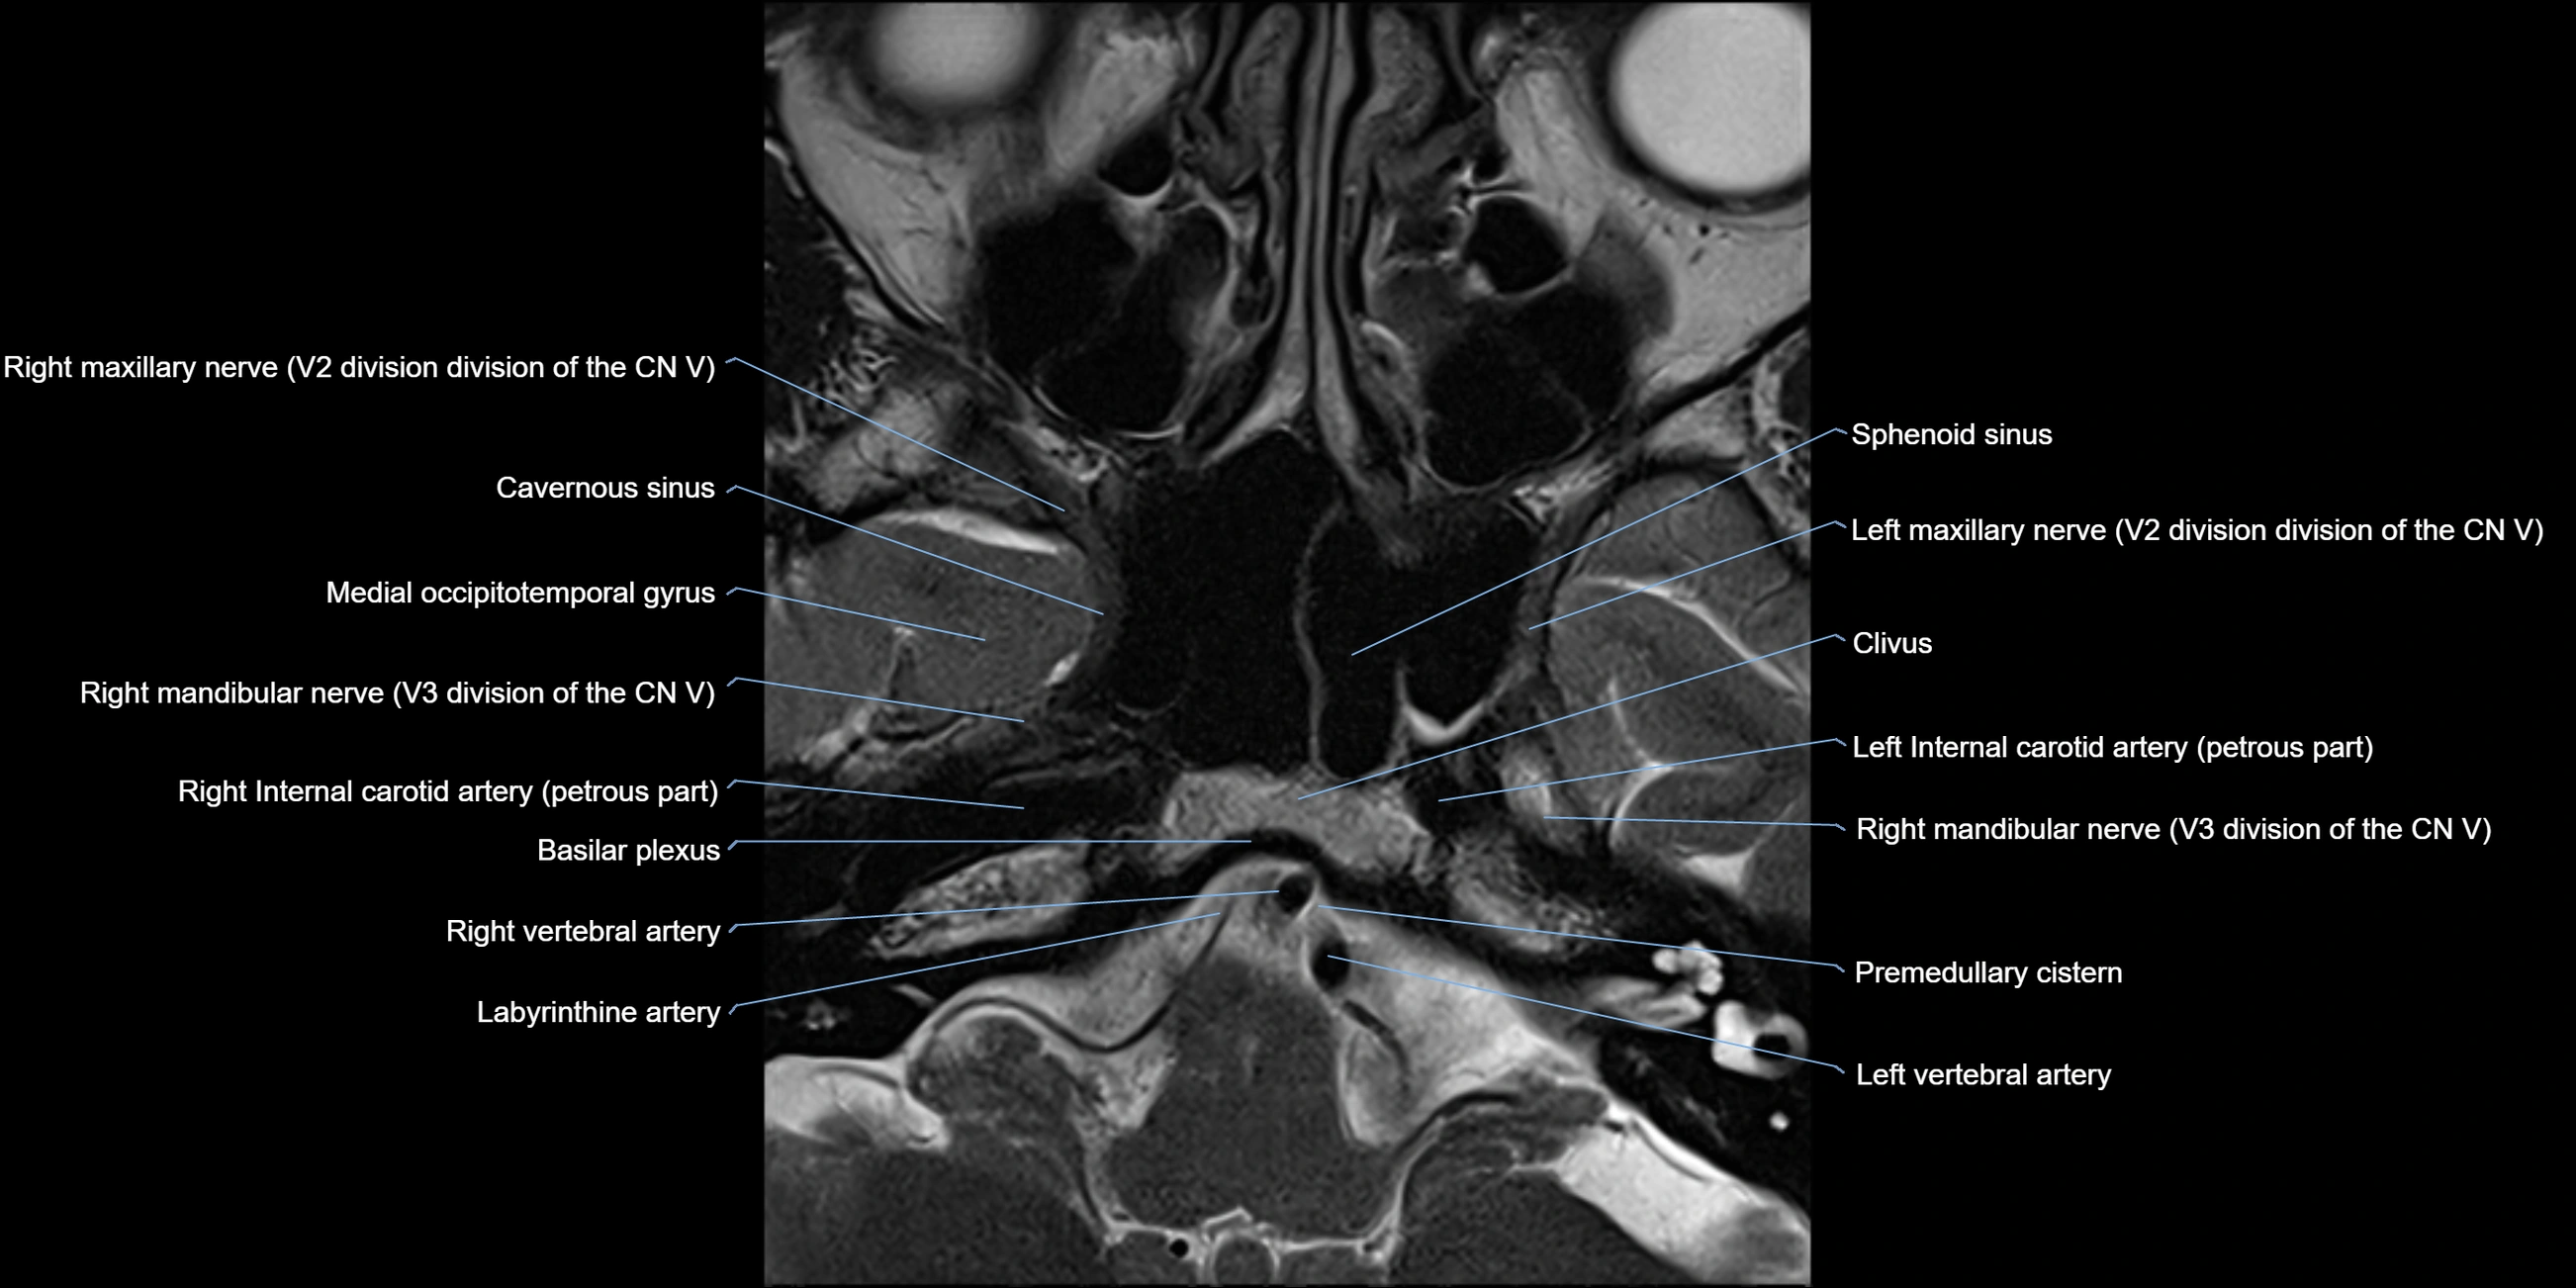

MRI images